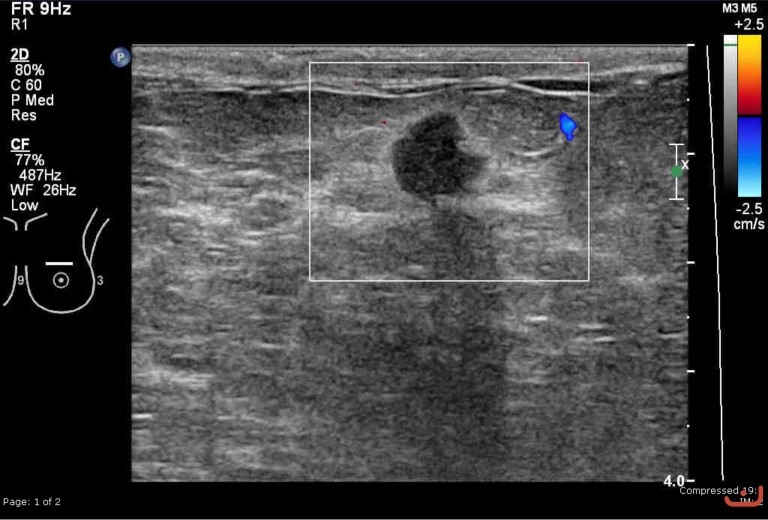

Malignant solid mass

Friday, 22 May 2015

212.73 KB (768 x 520 px)